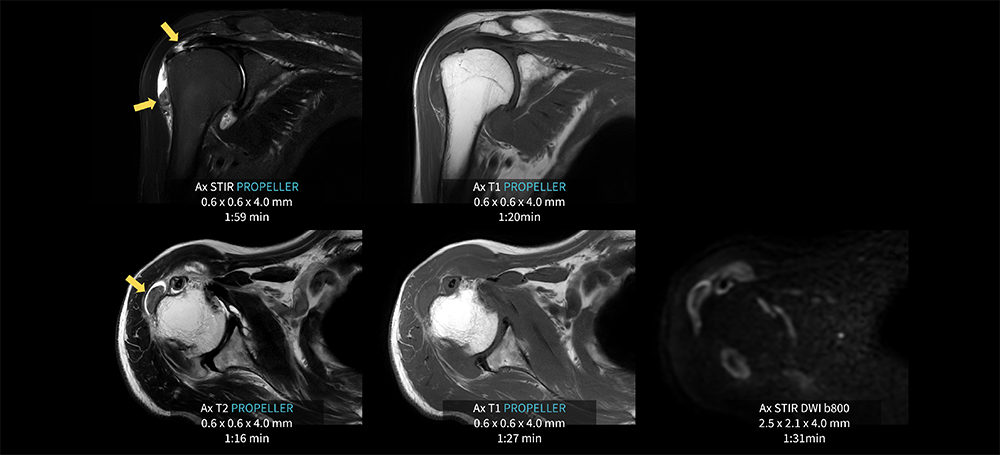

Case8 PROPELLER/変形性肩関節症

80代、男性。変形性肩関節症にてMRI検査を施行した。

関節液の貯留が見られ、棘上筋腱周囲にSTIR像にて高信号域が見られる。上腕骨骨頭外側では、貯留関節液内に10㎜大の低信号域を認め遊離体を疑う。AIR Recon DL併用のPROPELLERにより痛みや呼吸による肩関節周囲の動きの抑制が可能となり、各シーケンス1分台の短時間撮像を実現している。各シーケンスの短時間化のため発生した余剰時間にて、拡散強調像を追加し情報量を高めている。

MR30_Kariyatoyota_10.jpg図8 PROPELLER を用いた肩関節検査